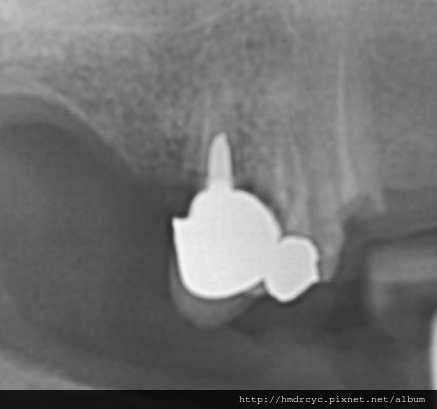

假牙必須利用X光片來更精確的判斷有沒有問題

在X光上面假牙是白色的影像

但X光片判讀困難 所以這部分必須仰賴醫師的專業

1. 蛀牙

蛀牙是常見的問題

X光上則是一個黑色的蛀洞可以參考蛀牙範圍

X光通常會有1-2mm的誤差

所以實際上牙齒裡的洞會比影像大

只要牙套底下出現X光可以辨別的蛀洞

未來繼續蛀牙的速度會很快

牙套內的牙齒也會流失的很嚴重